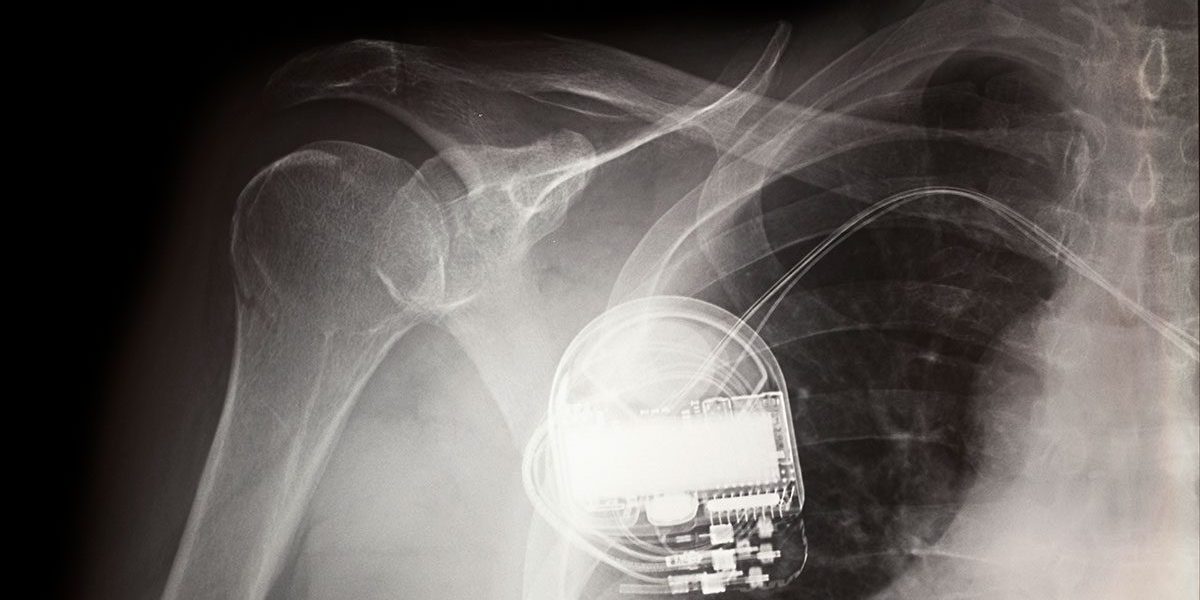

The human body is like a fortress. It protects your organs on the inside while rejecting foreign invaders and pushing them outside. Typically, that’s exactly what you’d want it to do, but sometimes, we need foreign materials to be accepted, like in the case of transplants, rods in damaged bones and pacemakers. So, when designing antibacterial coatings for medical devices, it’s important that they meet guidelines for biocompatibility including cleanliness, consistency and stability. Parylene has many advantages that make it a great choice for implanted medical devices.

Parylene has a long history of use as a protective coating for medical device biocompatibility and conforms to the USP Class VI and ISO 10993 standards. It is transparent, pin-hole free, and conforms precisely to any surface’s features. Parylene’s thickness is critically controlled and extremely consistent. It coats very thinly, on the order of microns, providing deep crevice penetration, and adds very little weight or volume. On the whole, Parylene works extremely well in most medical applications.

In a hospital setting, antimicrobial coatings for medical devices and instruments are vital for keeping them free of contamination. Parylene can withstand sterilization by E-beam, gamma ray, EtO, and autoclave, with the effects shown in Table 2 below. It protects against chemicals, moisture, and bodily fluids. Overall, Parylene protects the device from the body and the body from the device, helping to prevent premature and critical use device failure in the long term.

Parylene is a low-friction polymer coating that allows for easy sliding and serves as a dry lubricant. That slickness is important in many medical applications because increased friction typically means a procedure is more painful and takes longer to accomplish. Parylene is about as slippery as TeflonTM and has proven to be extremely useful for stents, syringes, catheters, needles, and other medical implants.

The US FDA has approved parylene with a Class VI biocompatibility rating suitable for human implantable devices, based on its performance in the USP Class VI grade and ISO 10993 group of standards. Not only does parylene meet FDA biocompatibility standards, it’s also chemically inert, highly conformable with very well controlled thickness, resistant to flaking, and is capable of withstanding the effects of multiple sterilization processes. With all of these capabilities and characteristics, parylene biobased polymer coatings are just what the doctor ordered.